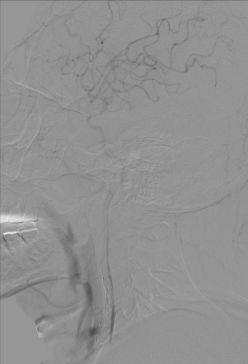

3. 颈内动脉C1段支架植入。

颈内动脉DSA提示颈内动脉狭窄,远端血流较差。 颈内动脉置入9mm-40mm Protege支架,收回保护伞后DSA提示血管再通良好,给予替罗非班7ml/h。 术后即刻查体NIHSS评分8分,给予替罗非班10ml/h泵入,持续24h。 术后第2天复查灌注成像提示双侧半球基本对称,CTA提示右侧颈内动脉以及大脑中动脉通畅。